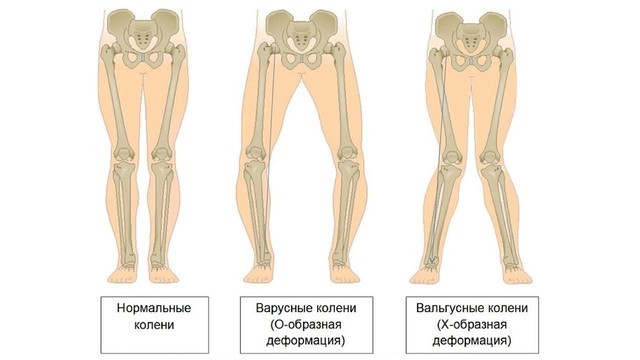

Деформация возникает за счет отека суставной сумки, разрастания остеофитов. При нарушении формы коленных суставов образуется Х- или О-образная деформация ног (рис. 4). При остеоартрозе пястно-фалангового сустава большого пальца стопы формируется пресловутая «косточка», которая уродует ногу и причиняет дискомфорт.